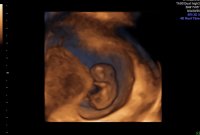

Lille bamsemums har nå blitt en minibaby ❤️ 10 uker i dag og alt ser fortsatt helt fint ut og vokser akkurat som hen skal :)